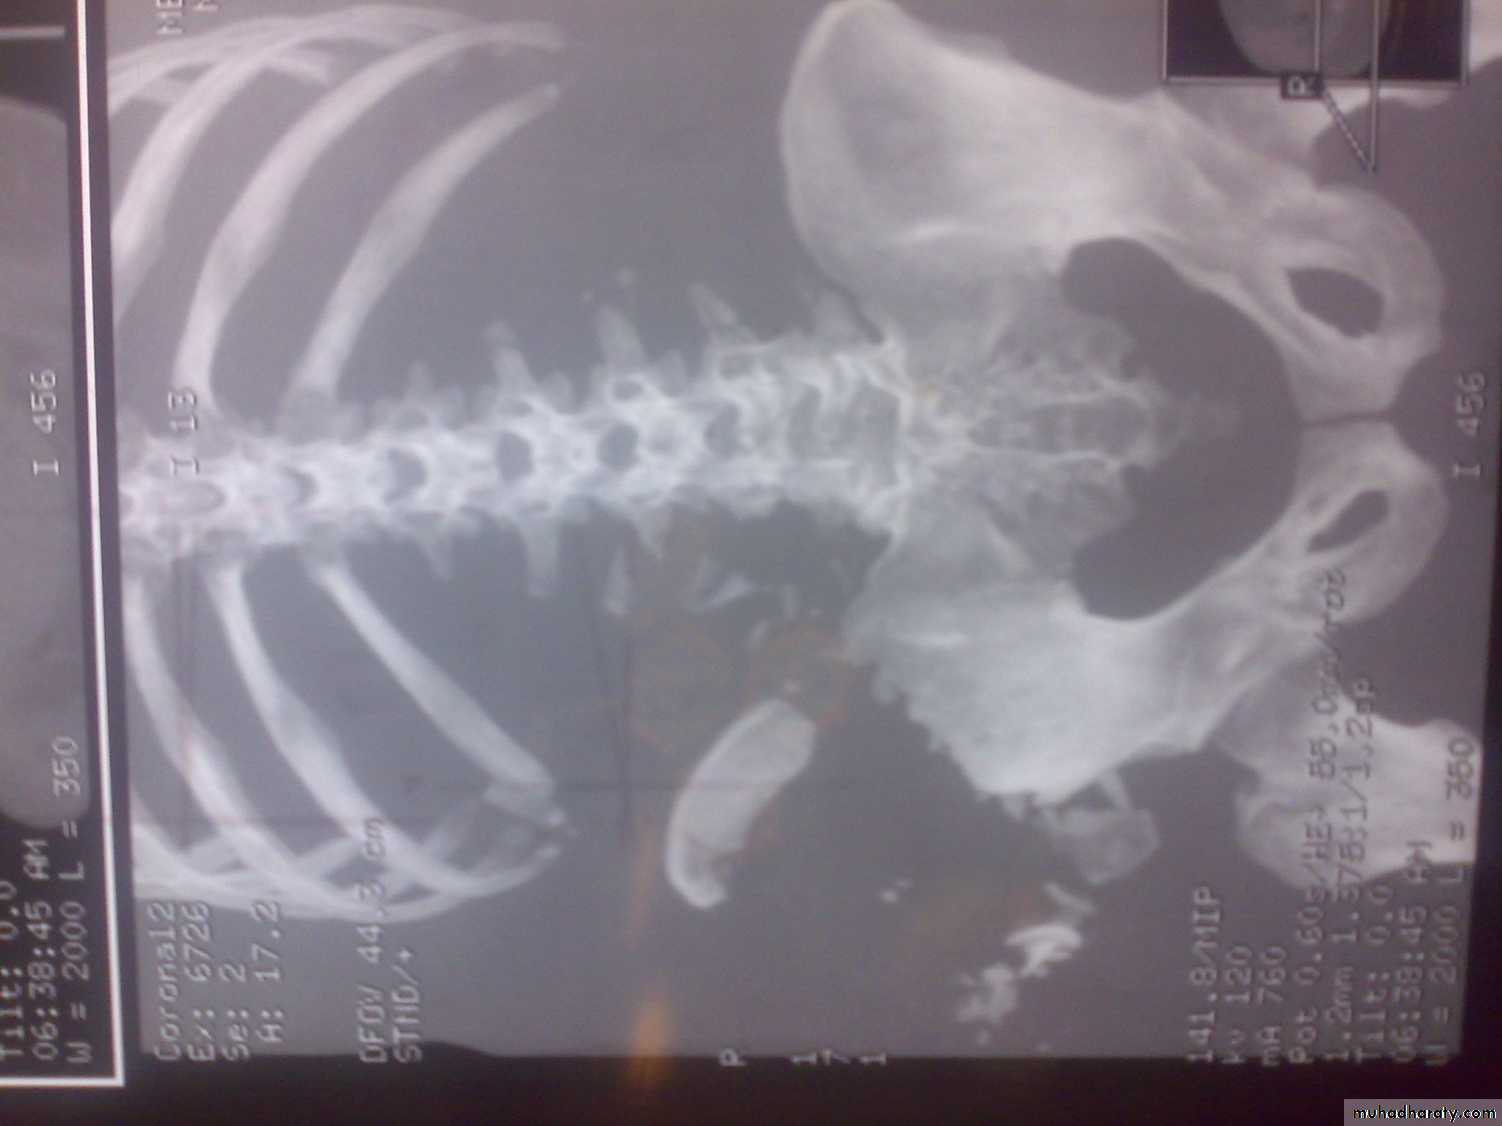

C-T scan

Indications:Segmental bone necrosis.

Depressed fracture in cancellous bone.

Small radiolucent lesion; eg oseoid osteoma.

Bone and soft tissue tumors.

Complex fractures of spine, pelvis, tarsal and carpal bones.

3-D reconstructed images.

Disadvantage: high radiation exposure.

3-D C-T in fracture pelvic ilium